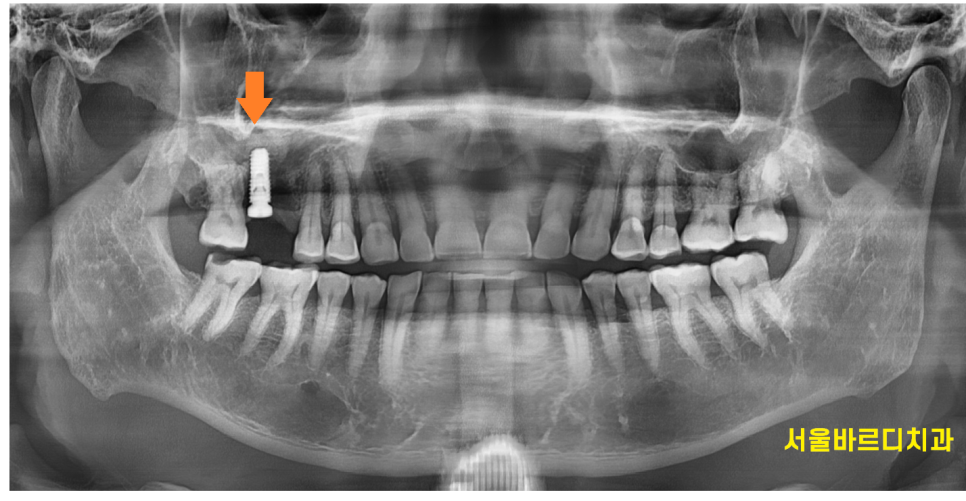

검사를 위해 촬영해본 x ray

오른쪽 위에 어금니 1개가 잇몸뼈가 심하게 녹아있습니다.

잇몸뼈가 남아있는 양 옆 치아와 비교해보아도

유독 문제 치아 주변으로만 까만 것이 보이실겁니다.

뼈가 다 녹아서 그렇습니다.

x-ray 상에서 뼈가 너무 많이 녹아있어

임플란트.. 바로는 어렵겠다... 감이 왔습니다.